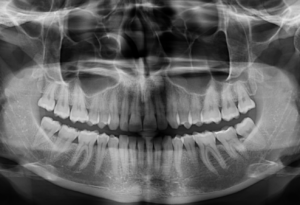

En la radiografía panorámica (Figura 1), se aprecia pieza supernumeraria invertida proyectada en zona anterior del maxilar superior.

Radiografia Panorámica